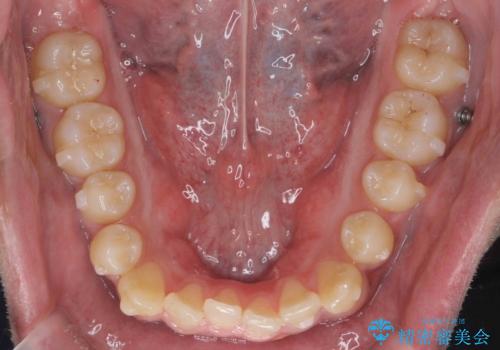

骨格性の受け口 非抜歯で下の歯を後ろに下げる インビザラインで インプラント矯正

治療により受け口が改善し、下あごの輪郭も若干後ろに下がった印象になりました。

当院では下の歯を後ろに下げるため矯正用ミニスクリューを用いてしっかり移動を行う等ご説明をし、治療開始しました。